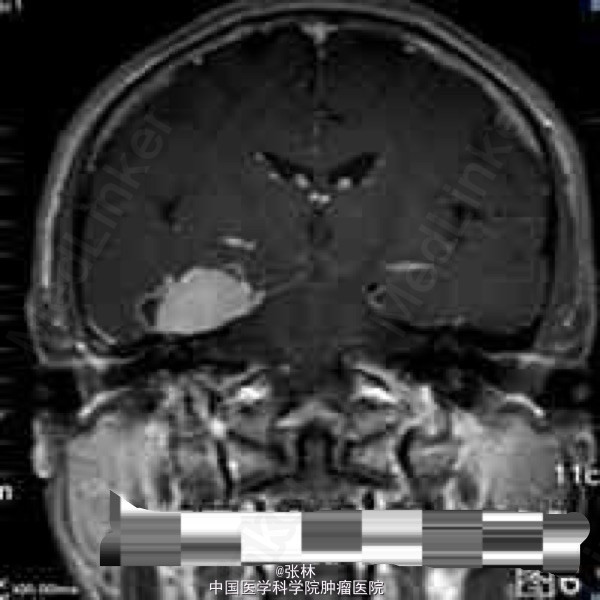

CT表现:右侧颅中窝可见一不规则肿块,呈等密度,内部密度均匀,CT值约37HU,肿块边界尚清晰,略成分叶状,与邻近骨质呈广基底相连,最大截面3.3cm×3.8cm,边缘处可见带状低密度影,边界清晰,CT值约16HU。肿块周边脑组织水肿,密度略减低。肿块周边骨质未见增厚硬化或变薄等异常改变(图1-2)。 CT诊断:右侧颅中窝肿块,伴周围脑组织水肿,建议进一步检查。 MRI表现:右侧颅中窝可见一不规则肿块,最大截面3.6cm×4.1cm,肿块边界清晰,成分叶状,与邻近骨质呈广基底相连(图5-6),在T1WI上呈等信号,在T2WI上呈略高信号;肿块边缘可见不规则液性信号带,在T1WI上呈低信号,在T2WI上呈高信号,与脑组织分界清楚(图3-4);肿块前方颞叶部分脑组织可见片状异常信号,在T1WI上呈稍低信号,在T2WI上呈略高信号,边缘模糊(图3-4);注射对比剂后,肿块实性部分明显强化,并可见“脑膜尾征”,而液性信号带未见强化(图5-6),肿块前方颞叶的片状异常信号未见强化。 MRI诊断:右侧颅中窝脑膜瘤,部分囊变,伴周围脑组织水肿。 手术病理结果:非典型性脑膜瘤,WHO分级II级。 讨论: 脑膜瘤是颅内仅次于胶质瘤的常见原发肿瘤,发病率占颅内肿瘤的16%~17%,在颅内脑外原发肿瘤中占第一位。它起源于脑膜的蛛网膜内皮细胞,常见于富含蛛网膜颗粒与蛛网膜绒毛的地方,以上矢状窦旁、大脑凸面、大脑镰、蝶骨嵴、鞍结节、嗅沟、小脑桥脑角区及小脑幕等部位多见。